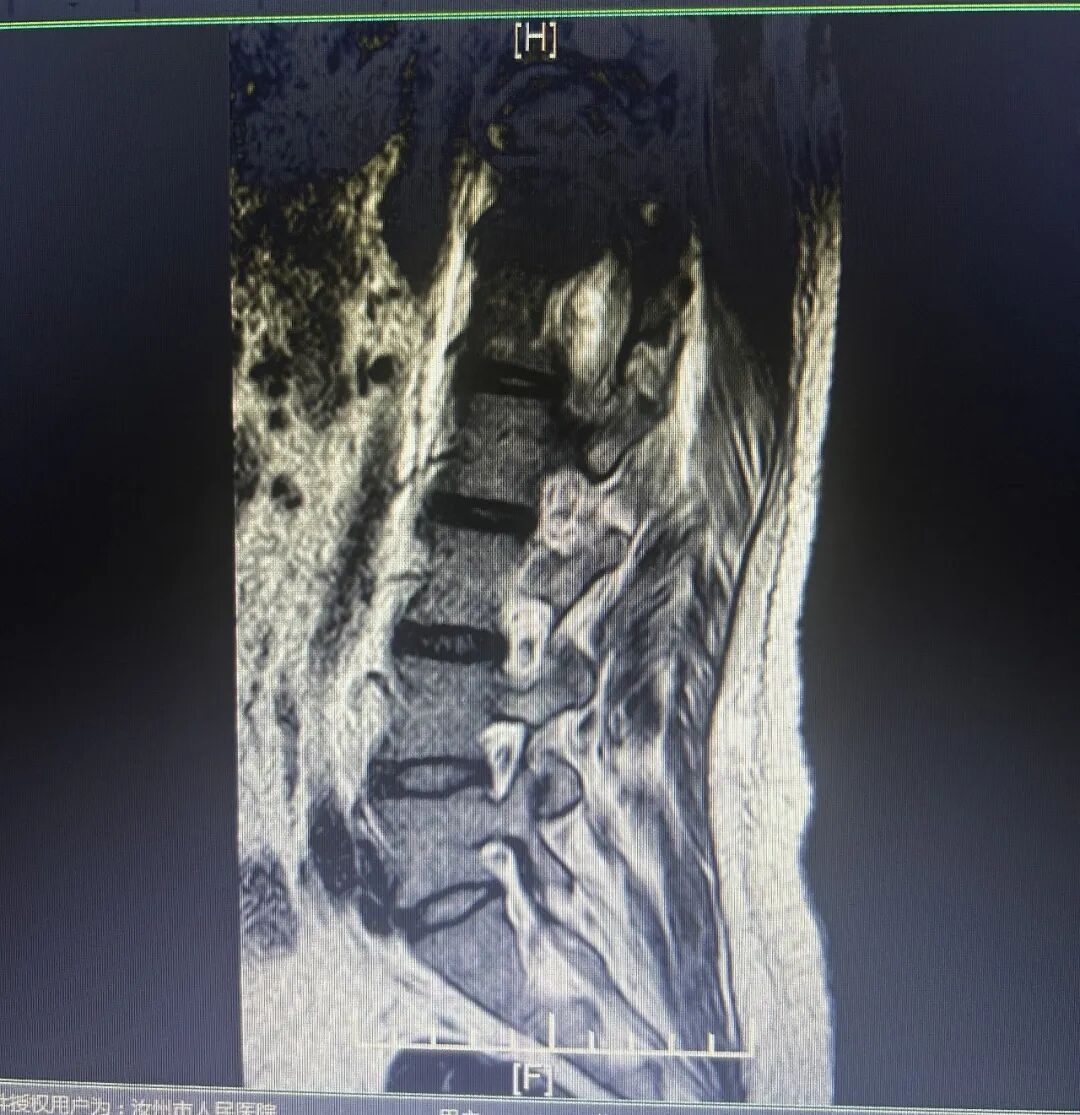

手术后胸椎、腰椎

最终,经过近3个小时的鏖战,显微镜下成功将患者胸腰段脊髓肿瘤完整切除,周围的脊髓完整